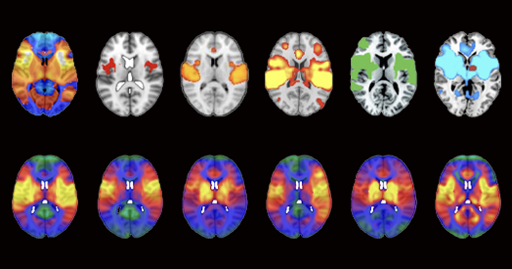

Aleyan@lemmy.world to science@lemmy.worldEnglish · 18 hours agoMore than 200 published studies and at least 7 ongoing clinical trials rely on potentially faulty brain network maps, according to a study published in Nature Neurosciencewww.thetransmitter.orgexternal-linkmessage-square0fedilinkarrow-up125arrow-down11file-text

arrow-up124arrow-down1external-linkMore than 200 published studies and at least 7 ongoing clinical trials rely on potentially faulty brain network maps, according to a study published in Nature Neurosciencewww.thetransmitter.orgAleyan@lemmy.world to science@lemmy.worldEnglish · 18 hours agomessage-square0fedilinkfile-text